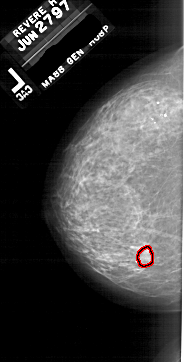

A_1784_1.LEFT_CC

LEFT_CC LINES 5791 PIXELS_PER_LINE 2941 BITS_PER_PIXEL 12 RESOLUTION 43.5 OVERLAY

FILE: A_1784_1.LEFT_CC.OVERLAY

TOTAL_ABNORMALITIES 1

ABNORMALITY 1

LESION_TYPE MASS SHAPE LOBULATED MARGINS ILL_DEFINED

ASSESSMENT 4

SUBTLETY 4

PATHOLOGY BENIGN

TOTAL_OUTLINES 1

BOUNDARY